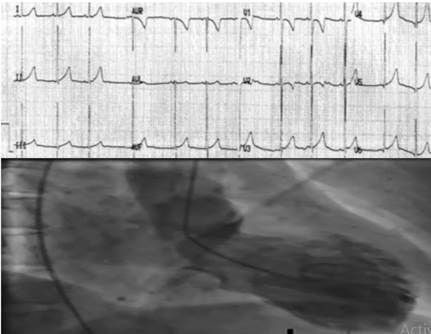

El "síndrome del corazón roto" (Takotsubo) y el Patrón de Breijo se aprecian correctamente en la siguiente imagen, 12,13) (Figura 7).

También es conocido la existencia de un síndrome de Wolf-Parkinson-White asociado con un Patrón de Breijo electrocardiográfico, como se puede ver a continuación (Figura 8).

El último electrocardiograma realizado con Patrón de Breijo, en un hombre que lamentablemente murió debido a que no pudo recuperarse de una muerte súbita.

El rastreo electrocardiográfico se consideró dentro de límites aceptables y sus médicos decidieron enviarlo a casa (Figura 11).